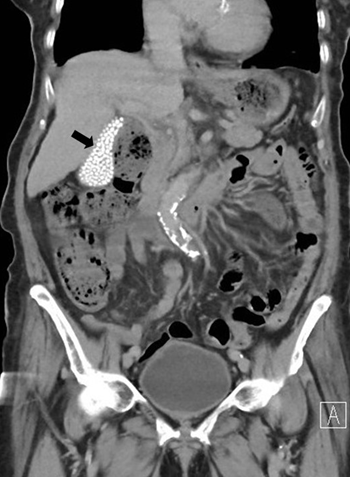

A bag of stones found incidentally

A 91-year-old woman presented with right flank pain for two days without fever, dysuria, trauma, or recent falls. Physical examination revealed no costovertebral angle tenderness. Laboratory tests showed an elevated C-reactive protein level of 3.6 mg/dL without leukocytosis. Urinalysis demonstrated pyuria and bacteriuria. She was treated empirically for acute pyelonephritis with intravenous cefoxitin, and urine culture later grew Escherichia coli sensitive to cephalosporins. Abdominal computed tomography (CT) revealed rupture of a right renal cyst. Incidentally, the gallbladder was filled with multiple small, round, hyperdense calculi, producing a striking "bag of stones" appearance (image 1, arrow). These findings were consistent with asymptomatic cholelithiasis. The patient´s flank pain improved after a 7-day course of antibiotics. She was discharged in stable condition, and outpatient follow-up was unremarkable. Asymptomatic gallstones are commonly detected incidentally, and most patients remain symptom-free; therefore, expectant management is generally recommended. Prophylactic cholecystectomy is reserved for selected high-risk patients, such as those with porcelain gallbladder, large gallstones (>3 cm), anomalous pancreaticobiliary ductal junctions, gallbladder adenomas, or underlying hemolytic disorders.